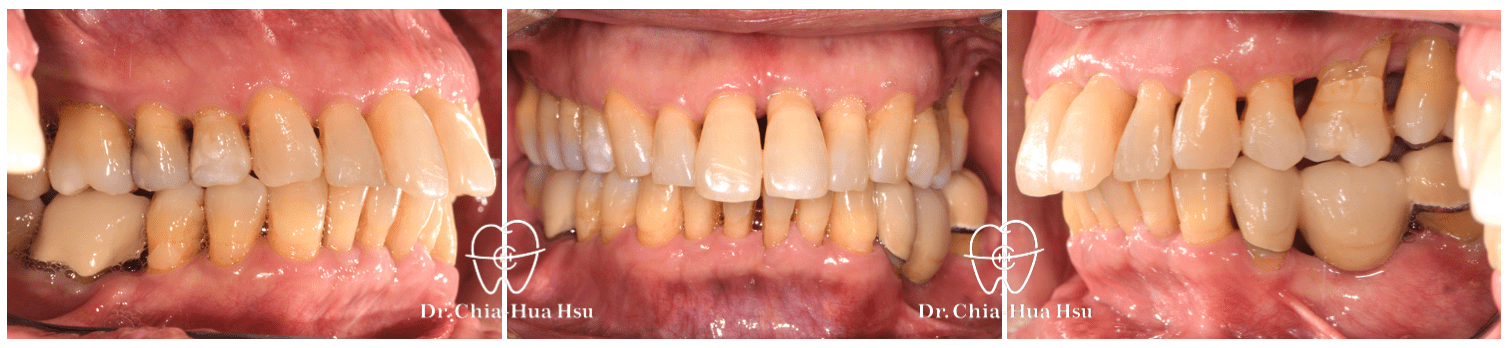

• 治療方式:在病患牙周治療結束後,與患者討論治療方案,最後使用對牙周健康友善的隱適美治療,並搭配上顎骨釘的使用,來改善患者的暴牙與齒列不正。後續也透過美學樹脂補牙來處理患者下顎門牙黑三角縫的問題。

治療前

治療後

矯正治療中期:使用隱適美搭配骨釘來讓上排齒列退後。隱適美治療給予的矯正力量輕柔和緩,也方便病人清潔牙齒,非常適合牙周病的患者。